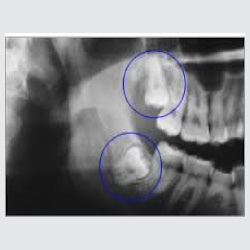

• Wisdom teeth extraction is recommended in case when there is inappropriate space in the jaw to accommodate a third molar or if it is growing sideways or if it is giving a regular cheek bite etc

• Impacted wisdom teeth lead to pain, swelling, inflammation, difficulty in mouth opening etc. It can also sometimes lead to a development of cyst/tumour